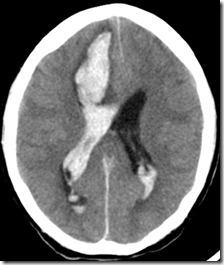

Fig 3: A -CT scan and B –MRI showing a large area of hemorrhage (white in CT and black in MRI)